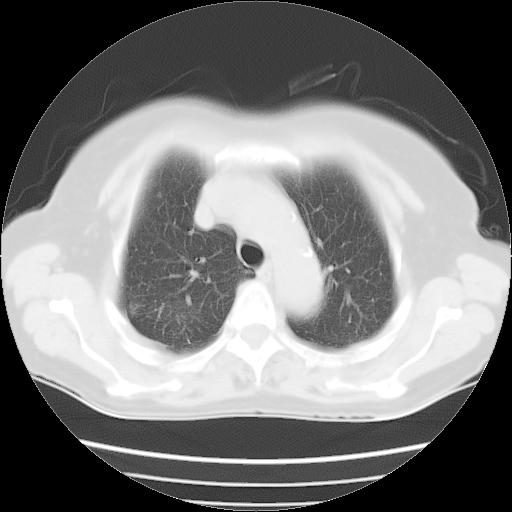

以下是引用夏季在2007-9-18 11:00:00的发言:[br]1。右肺肿块,周围有短毛刺,肺门侧有血管与其相连,胸壁侧有胸膜凹陷征,考虑周围性肺癌 2。左侧甲状腺软组织肿块,内有高密度钙化灶,考虑左侧甲状腺腺瘤。

以下是引用卜一在2007-9-18 14:41:00的发言:[br]右肺肿块:毛刺+胸膜凹陷征+供血血管+浅分叶+强化。支持:周围性肺癌 !另:左侧甲状腺腺瘤!